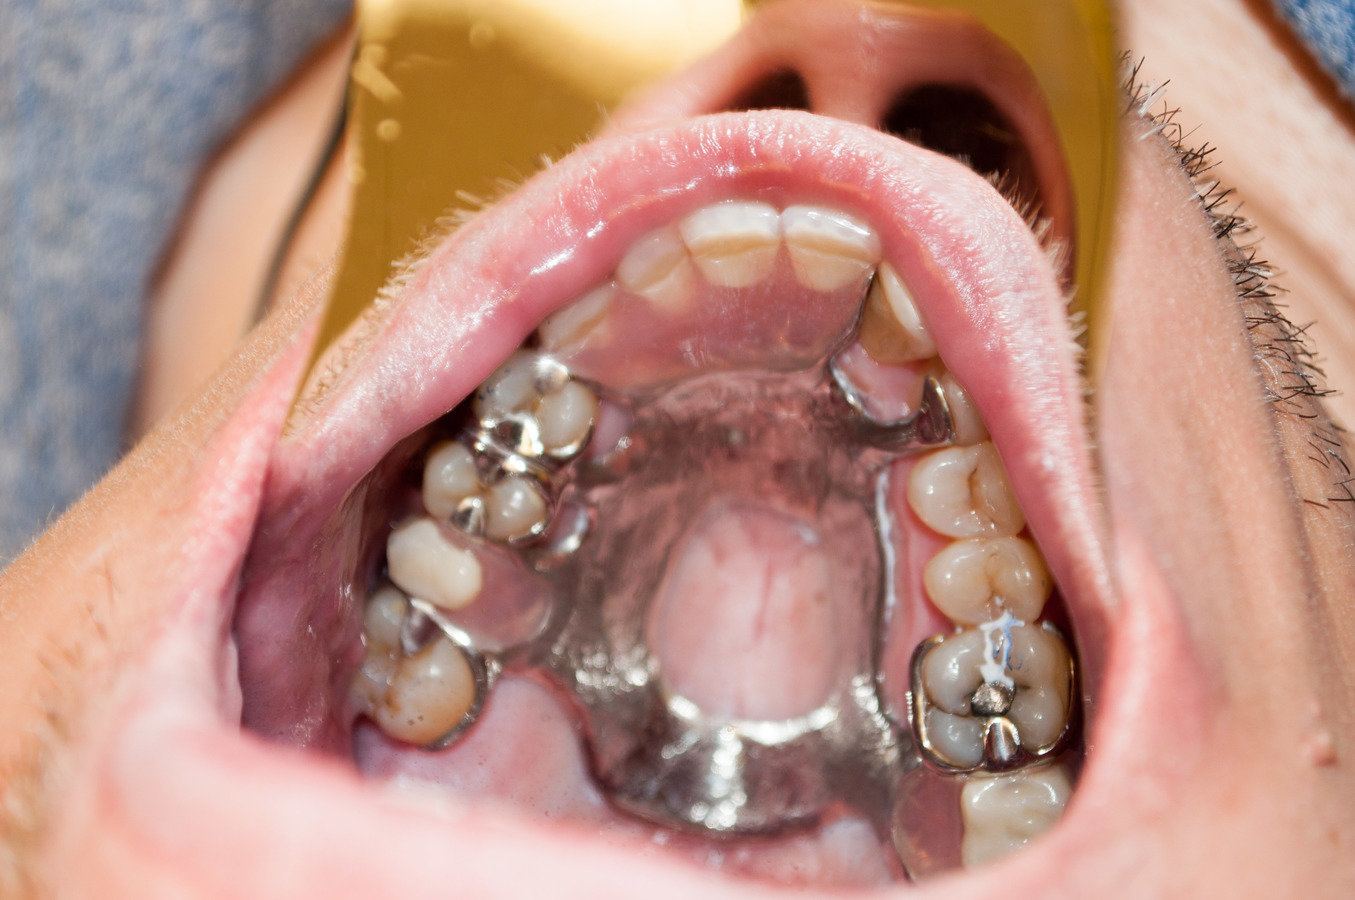

Stage 2: Prepare for Teeth

- Adult Orthodontic Therapy to close spaces

- Fabricate Maxillary RPD